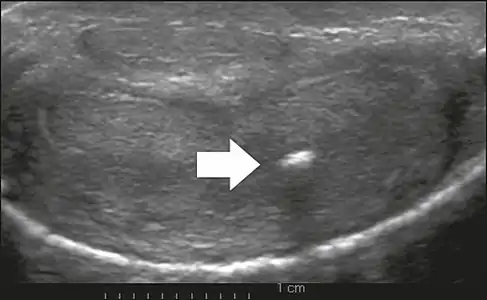

La ultrasonografia peniană, aspectul tipic este îngroșarea focală hiperecogenă a tunicii albuginea. Datorită calcificărilor asociate, imagistica pacienților cu boala Peyronie prezintă umbrire acustică, așa cum este ilustrat în figurile de mai jos. Rezultatele mai puțin frecvente, atribuite stadiilor anterioare ale bolii (fibroză încă ușoară), sunt leziunile hipoecogene cu îngroșare focală a țesuturilor paracavernare, îngroșarea focală ecografică a tunicii fără umbrire acustică posterioară, leziunile izoecogene retractile cu atenuare posterioară a fasciculului și pierderea focală a continuității tunicii albuginea. În studiul Doppler, fluxul crescut în jurul plăcilor poate sugera activitate inflamatorie, iar absența fluxului poate sugera stabilitatea bolii. Ecografia este utilă pentru identificarea leziunilor și pentru a determina relația acestora cu pachetul neurovascular. Persoanele cu boala Peyronie se pot prezenta cu disfuncție erectilă, adesea legată de scurgerea venoasă, din cauza drenajului insuficient la locul plăcii. Deși plăcile sunt mai frecvente pe dosul penisului, ele pot fi văzute și pe fața ventrală, pe fața laterală sau pe sept. [10]

Ecografie transversală a penisului, (ventral), în porțiunea mijlocie a acestuia. De remarcat în ecografie, imaginea acustică posterioară întunecată ce corespunde cu calcifierea (săgeată) din corpul cavernos stâng.[10]